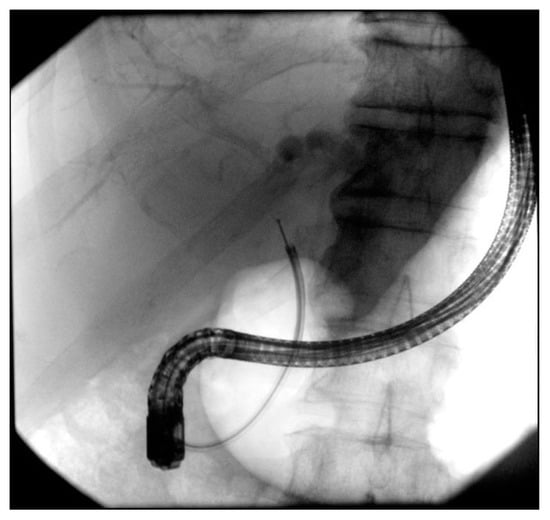

4.1. ERCP in Distal Strictures

- Dumonceau, J.M.; Tringali, A.; Papanikolaou, I.S.; Blero, D.; Mangiavillano, B.; Schmidt, A.; Vanbiervliet, G.; Costamagna, G.; Devière, J.; García-Cano, J.; et al. Endoscopic biliary stenting: Indications, choice of stents, and results: European Society of Gastrointestinal Endoscopy (ESGE) Clinical Guideline—Updated October 2017. Endoscopy 2018, 50, 910–930. [Google Scholar] [CrossRef]

- Moole, H.; Jaeger, A.; Cashman, M.; Volmar, F.H.; Dhillon, S.; Bechtold, M.L.; Puli, S.R. Are self-expandable metal stents superior to plastic stents in palliating malignant distal biliary strictures? A meta-analysis and systematic review. Med. J. Armed Forces India 2017, 73, 42–48. [Google Scholar] [CrossRef] [PubMed]

- Zorrón, P.L.; de Moura, E.G.; Bernardo, W.M.; Baracat, F.I.; Mendonça, E.Q.; Kondo, A.; Luz, G.Q.; Júnior, C.K.F.; Artifon, E.L.d.A. Endoscopic stenting for inoperable malignant biliary obstruction: A systematic review and meta-analysis. World J Gastroenterol. 2015, 21, 13374–13385. [Google Scholar]